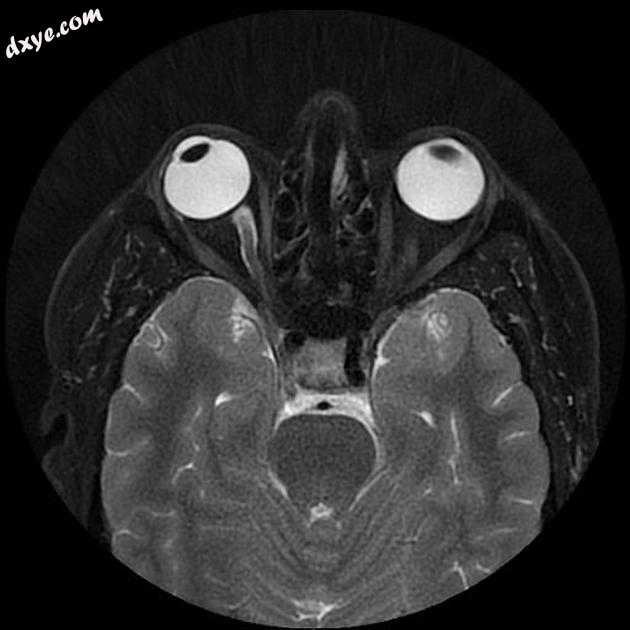

Axial FIESTA

5.jpeg

MRI 序列显示右侧颈内动脉的部分血栓囊状动脉瘤位于 C6/7 节段的交界处,大小为 11 x 7 毫米,颈部为 2.5 毫米,压迫动眼神经 (III) 的相邻节段,在 T1 上清晰可见和 FIESTA 序列。

位于 C6/7 交界处的右侧颈内动脉部分血栓囊状动脉瘤的 MRI 特征,压迫同侧动眼神经 (III)。